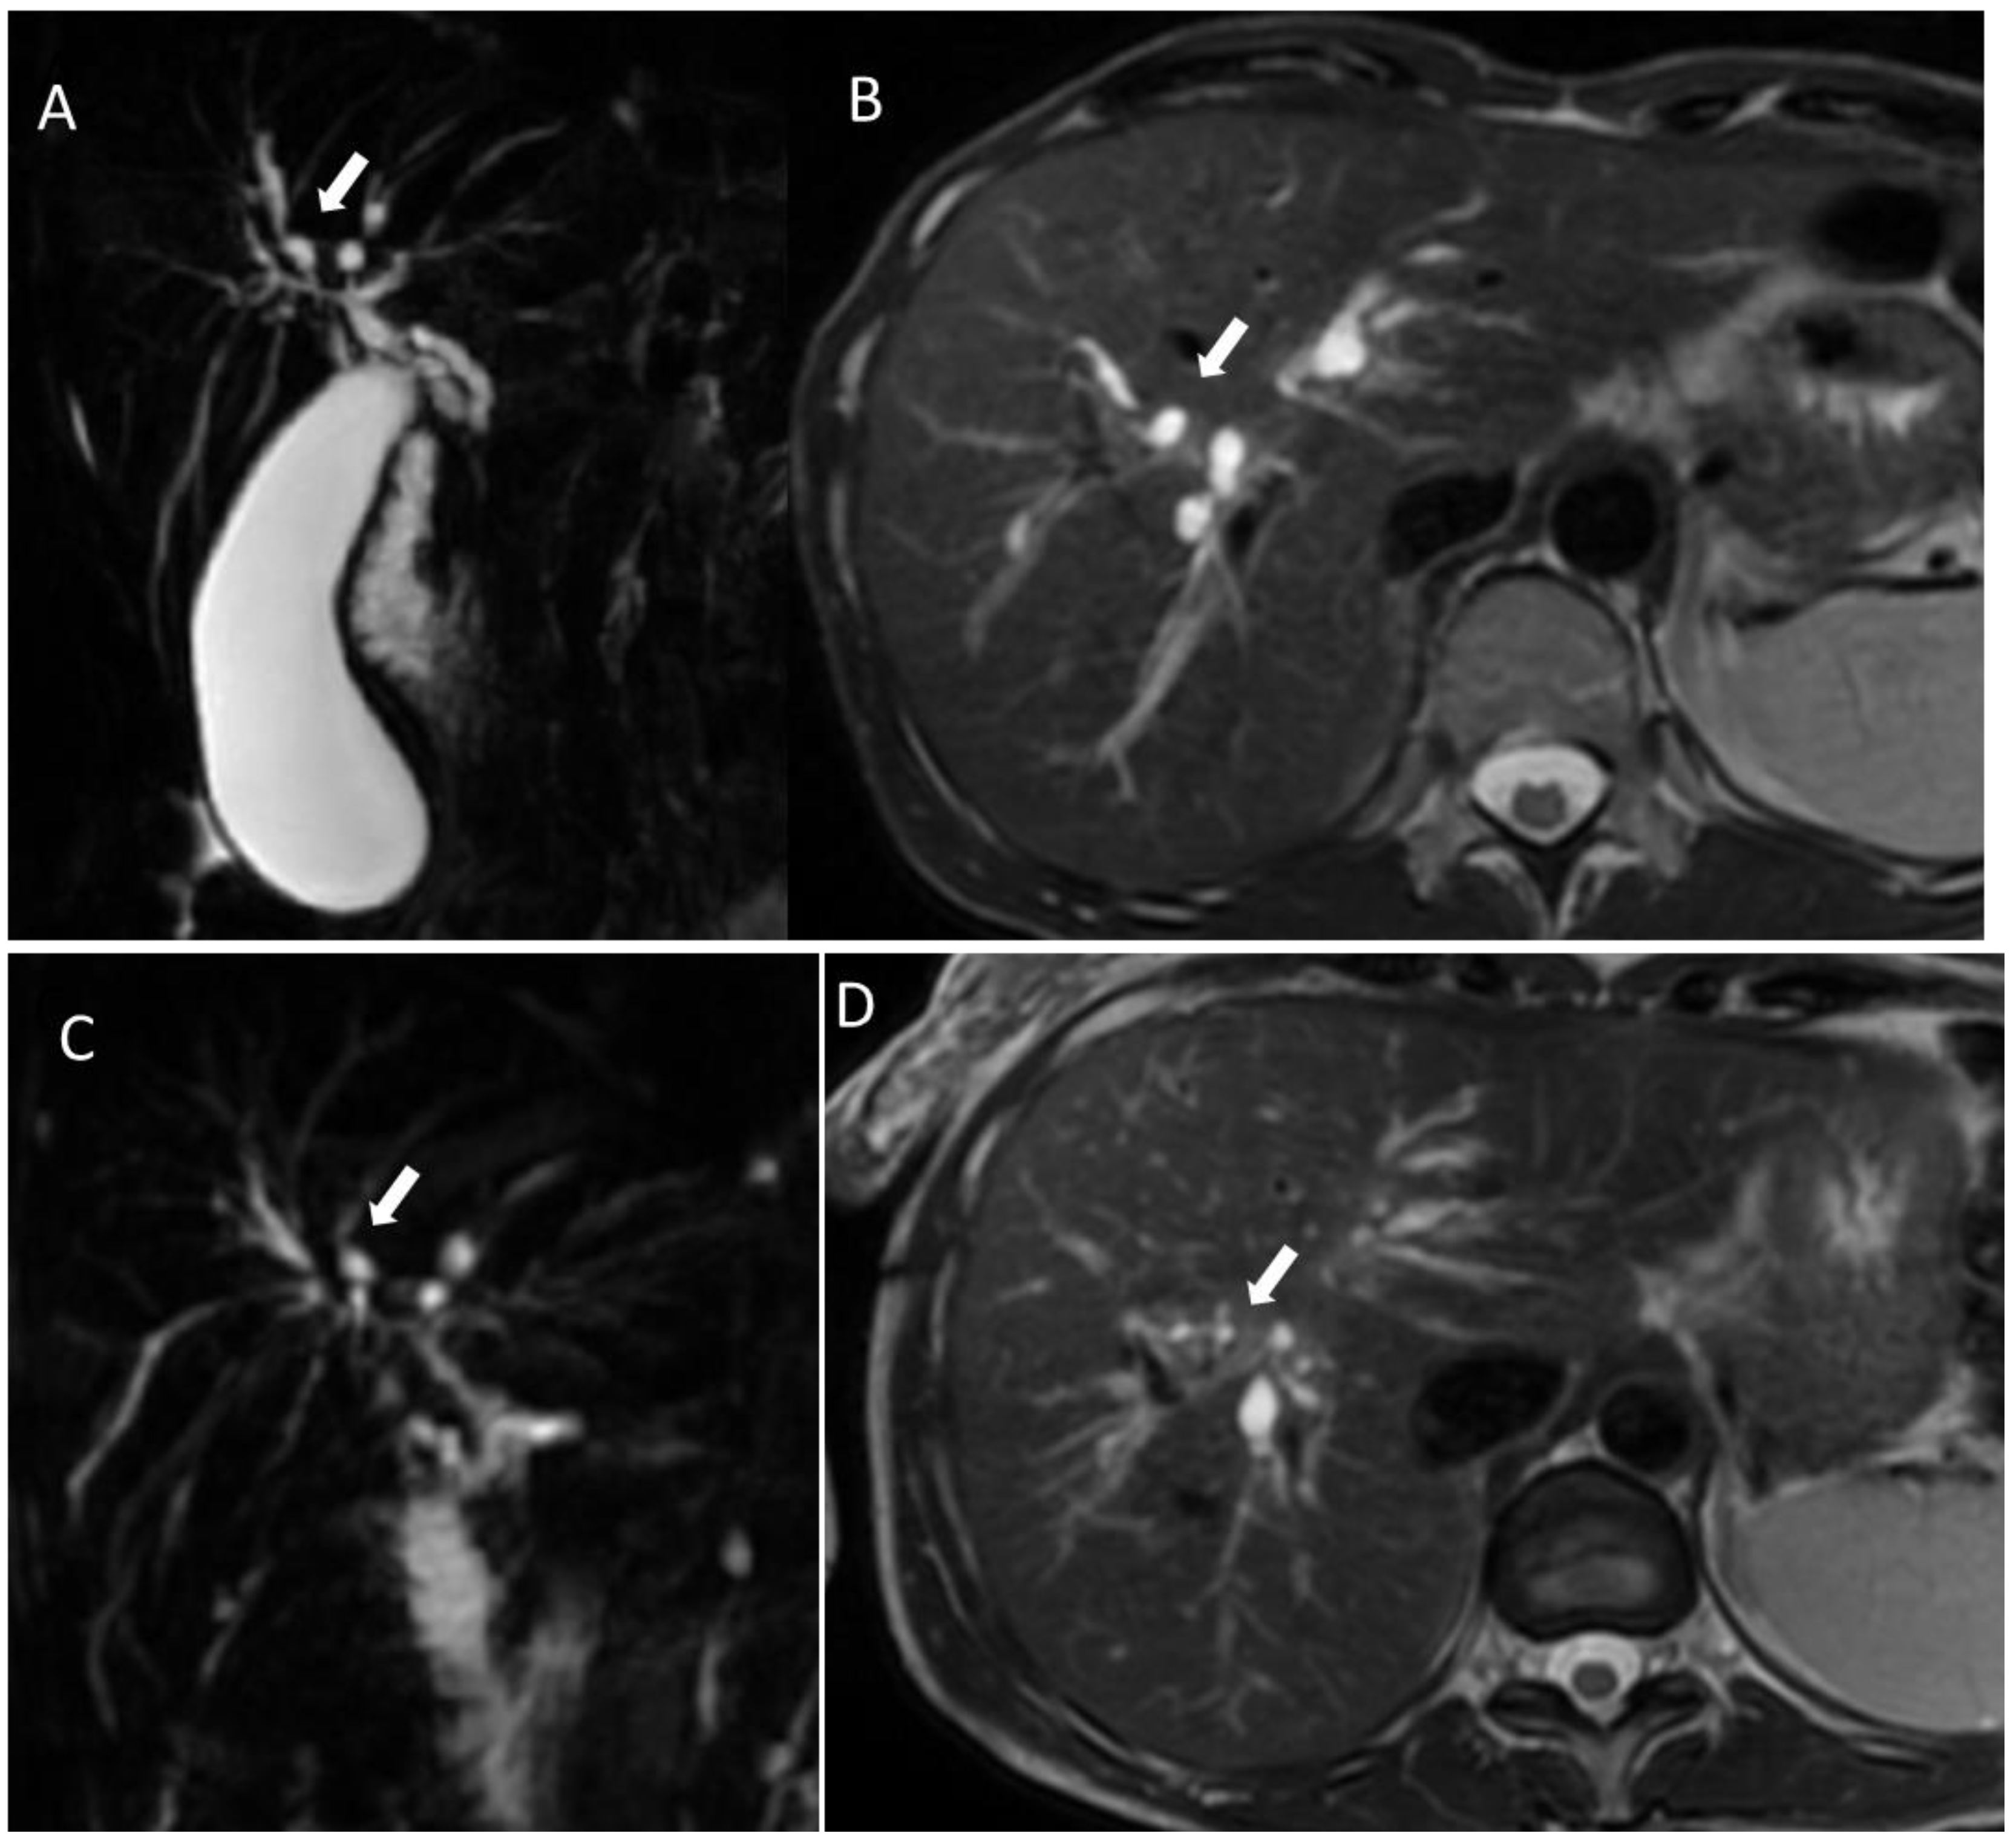

6.4. Hepatobiliary Mucinous Cystic Neoplasm

6.5. Diagnostic Management